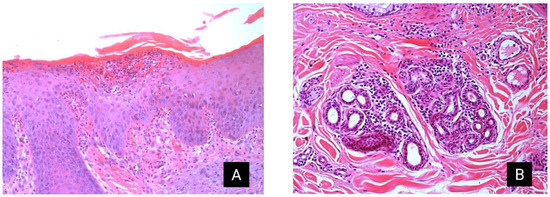

The histological changes in donkeys 3, 4, and 5 were characterized by moderate superficial dermatitis with irregular acanthosis of the epidermis and pronounced diffuse orthokeratotic hyperkeratosis. Furthermore, multifocal areas with crusts, moderate infiltration of intact and degenerated neutrophils (intraepidermal pustules), and moderate vacuolar degeneration of epidermal keratinocytes were observed. Moderate multifocal inflammatory infiltration of lymphocytes, plasma cells, and occasional neutrophils and eosinophils were observed in the superficial dermis (Figure 3). Areas with moderate multifocal degeneration of collagen fibers and a few macrophages with intracytoplasmic granular black pigment (pigment incontinence) were also observed. Toluidine blue, Gram, and Warthin–Starry staining did not reveal the presence of mast cells, Gram-negative and Gram-positive bacteria, or spirochetes.

Figure 3. Allergic dermatitis in Pêga donkeys. (A) Haired skin, focal area of intraepidermal pustule filled with moderated intact and degenerated neutrophils, and swollen keratinocytes with vacuolated cytoplasm (edema). This pustule is covered by moderate keratin, cellular debris, and rare erythrocytes (crust). Multifocally, on the superficial dermis, there are moderate numbers of neutrophils, lymphocytes, plasma cells, and eosinophils. Furthermore, severe diffuse irregular acanthosis and moderate diffuse orthokeratotic hyperkeratosis are observed in the epidermis. Using H&E staining. (B) Haired skin: multifocally in the mid-dermis and surrounding adnexa, there is severe inflammatory infiltration of lymphocytes, plasma cells, neutrophils, and eosinophils. H&E, hematoxylin and eosin.